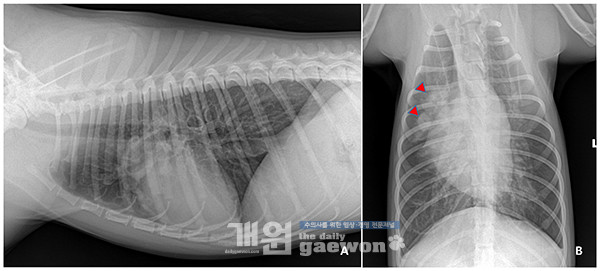

혈액검사에서는 CRP(C-Reactive Protein) 수치의 미약한 상승만이 있었고,그 외 수치는 정상이었다.일반 방사선 촬영을 통해 기관지 폐렴(Bronchopneumonia)과 기관지 확장증(Bronchiectasis)을 의심할 수 있었다[그림 1].